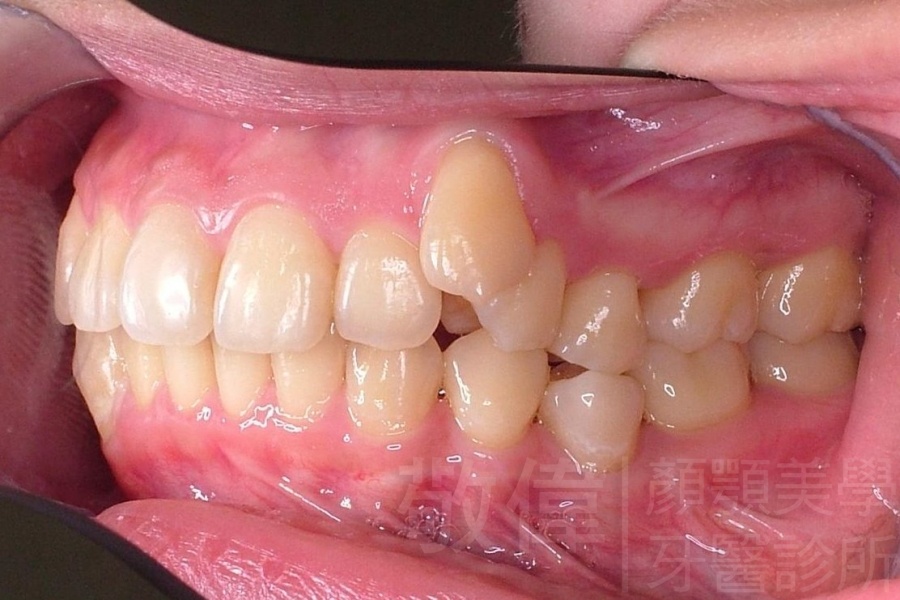

齒顏矯正/上顎暴牙且牙齒極度混亂

矯正前-右   矯正前-正   矯正前-左

矯正前-上   矯正前-下

<個案說明>

上顎暴牙且牙齒極度混亂,經由矯正之後,臉型大幅度改善,牙齒的排列更加的整齊健康。相較於之前眼神充滿精神,自信心展現無遺。